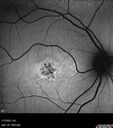

Stargardt Disease - Very Mild - 24 year old157 viewsThis patient has 3 different ABCA4 mutations. His mother and sister have stargardts and his father has RP. His sisters images are also on Retinagallery.com